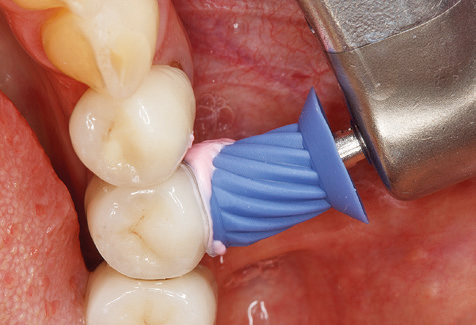

Fig. 4: Flexible probes with millimetre markings are recommended for the probing of dental implants (e.g. Colorvue Kit PCV11KIT6, Hu­Friedy). – Fig. 5a and b: A straight working tip (1P, W&H Dentalwerk Bürmoos GmbH) is a suitable instrument for use on all natural teeth. – Fig. 6: Curved working tips (3Pr/3Pl, W&H Dentalwerk Bürmoos GmbH) lend themselves to the processing of difficult-to-reach areas of the tooth and root surfaces (e.g. furcations). – Fig. 7: The tapered, hexagonal implant cleaning tip (1I, W&H Dentalwerk Bürmoos GmbH) permits atraumatic and efficient cleaning of the crown and abutment surfaces. – Fig. 8: Titanium and carbon curettes are suitable instruments for the manual cleaning of the implant surfaces.

Good illumination of the working field facilitates the process considerably. The system used by the authors achieves this thanks to a 5x LED ring integrated in the handpiece. Naturally, a range of working tips for different indications is also offered. A straight, universally employable tip is the basic instrument required for machine cleaning of natural teeth (Fig. 5a and b). Curved tips, which allow access to exposed furcations, are also available for hard-to-reach areas in the posterior region (Fig. 6).

Of course, working tips for the cleaning of implant surfaces are also indispensable for SPT in patients fitted with implants. The implant cleaning attachment on the system used here is characterised by its tapered, hexagonal design. This design allows light, atraumatic penetration of the peri-implant pocket and displays a good cleaning performance (Fig. 7).